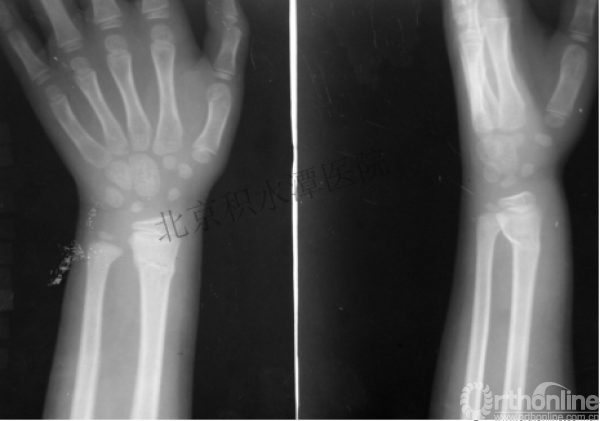

病例分享四

女孩、8岁,桡骨远端骨折

原始损伤

伤后1个月

伤后14个月